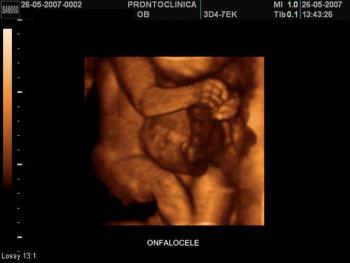

Onfalocele image in 3D-Fetus at 30 weeks gestation.